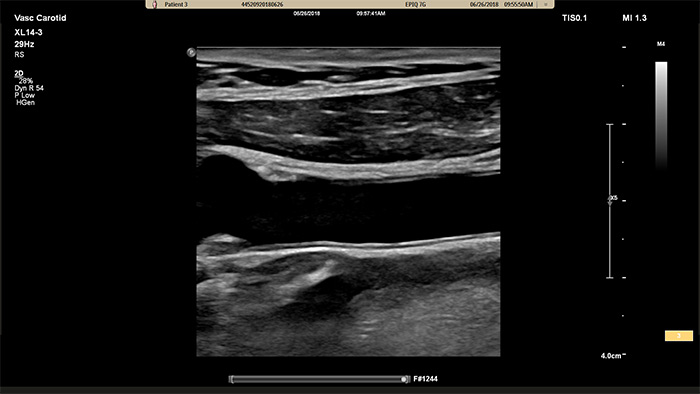

Der XL14-3 xMATRIX Schallkopf ermöglicht eine xPlane Bildgebung, die über den herkömmlichen Ansatz bei Gefässuntersuchungen hinausgeht und Echtzeitbilder gleichzeitig sowohl in der Längs- als auch Querebene bereitstellt. Wichtigster Vorteil: Bei der xPlane Bildgebung muss der Schallkopf zur Erfassung orthogonaler Ansichten nicht mehr rotiert werden. Mit einer einfachen Bewegung des Trackballs ist eine vollständige anatomische Beurteilung möglich – und die Untersuchungsdauer wird verkürzt.